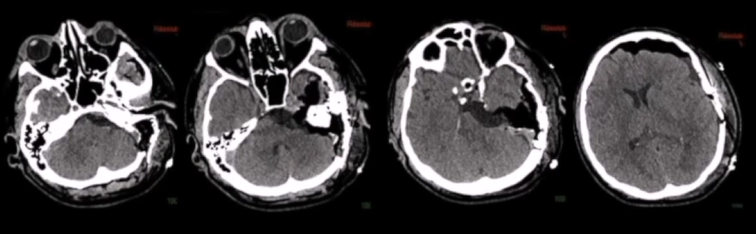

1、术前栓塞:用1毫升氰基丙烯酸酯胶(Glubran,Glubran-2,GEM,Viareggio,Italy)碘油(4ml of lipiodol)堵塞供血动脉,造影结果良好,无并发症。术后脑MR显示脑膜瘤部分断流,无脑水肿。

(患者脑血管造影图)

2、二天手术切除:颞部开颅术和前岩部切除术。脑膜瘤在肿瘤切除的不同阶段交替进行超声抽吸和周围结构的仔细解剖,从血管的角度观察,硬脑膜边缘被切断以完成肿瘤的断流。手术切除是完全的(辛普森I级切除),全部周围的颅神经IV、V、VII、VIII等均保存完好,患者术后神经功能完好。